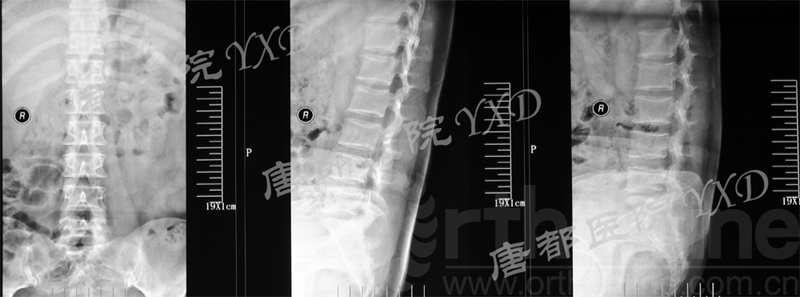

影像学检查:

诊断:腰椎间盘突出症术后复发

手术方案:显微镜辅助MI-TLIF腰椎翻修术